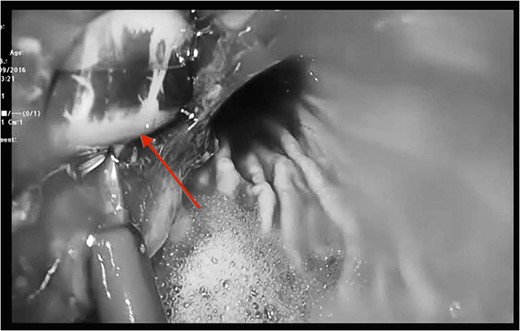

Cross section CT image demonstration the site of the band with no collection (red arrow).